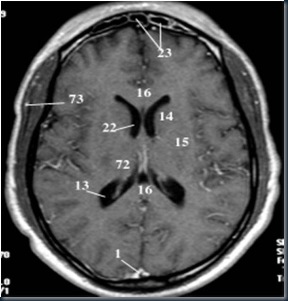

3. Potongan Axial Otak MRI

Keterangan gambar:

1. Sinus Sagital sup.

3. Lobus Frontal

4. Lobus Parietal

13. Ventrikel Lateral

16. Corpus Callosum

17. A. Serebri Media

20. Foramen Monro

22. Ventrikel III

23. Sinus Frontal

31. Aqueduct Serebri

43. Arteri Basiler

|

44. Ventrikel IV

45. Cerebellum

48. Pons

50. Sinus Sphenoid

52. Medulla

55. Sinus Sigmoid

63. Lidah

67. Fornix

72. Thalamus

73. A. Meningeal